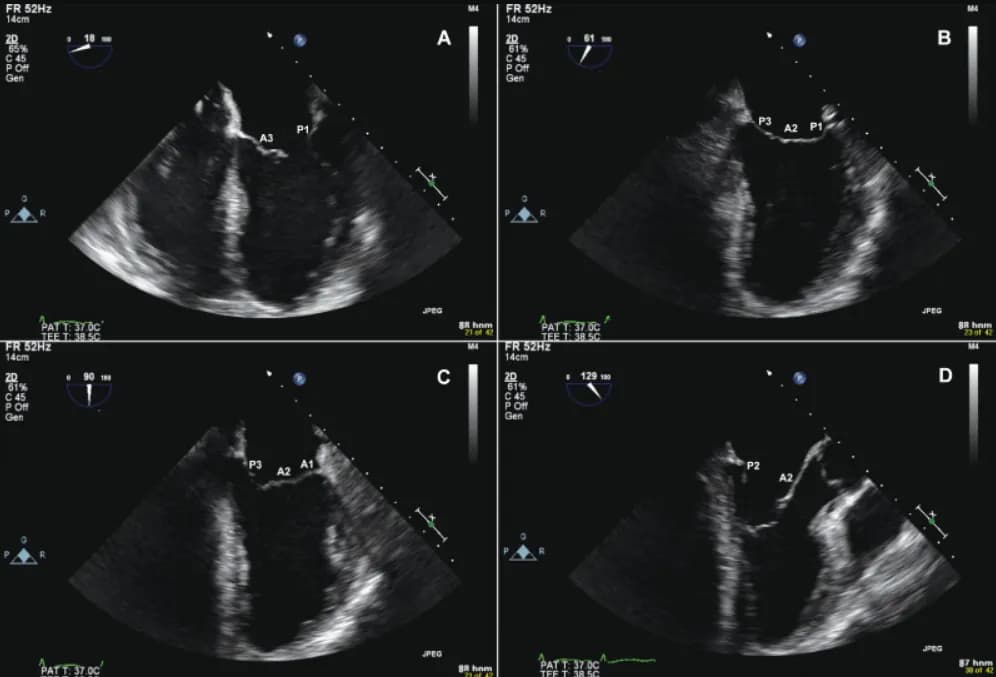

Siêu âm tim mạch qua thành ngực (TTE)

1. Quy trình siêu âm tim

Siêu âm tim mạch là một kỹ thuật chẩn đoán hình ảnh không xâm lấn, sử dụng sóng siêu âm để tạo ...